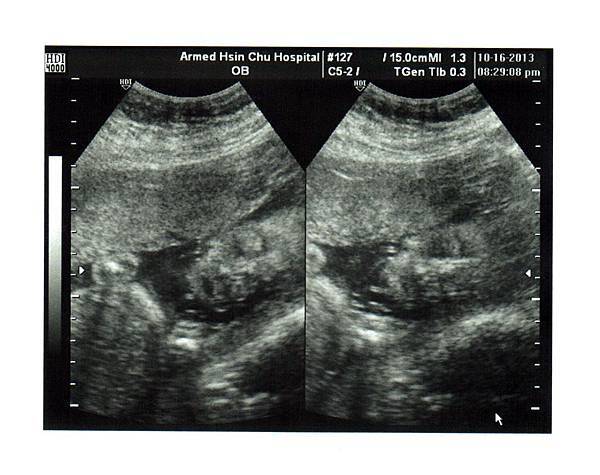

懷孕22 24週 22週禾馨懷寧林佳慧醫生高層次超音波 購物狂女王venus

懷孕 懷孕日記第25週 超音波照到好清楚的臉蛋唷 By妞 大野狼與小俏妞 痞客邦

金牌大肚日記 懷孕25周 第六次產檢 稀有品種 痞客邦

金牌二肚日記 第25周產檢紀錄 稀有品種 Pchome 個人新聞台